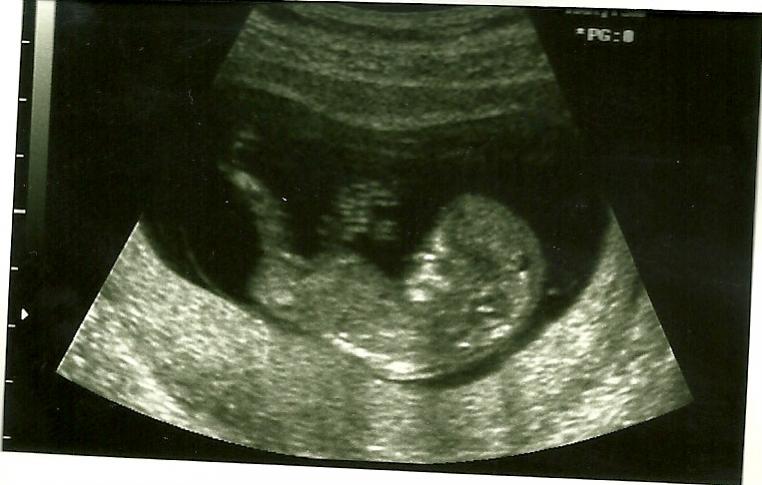

Do you see a nub? 12w2d

I went in for an u's today and babe is measuring 12w2d. I was intently focused on the nub area but didn't see a thing! I have three pics, but I still don't see a nub in any of them. Attachment 154Attachment 155Attachment 156Does anyone see anything that would lead them one direction or another? TIA!

I think pic 1 looks very flat! I'd guess girl:agree: